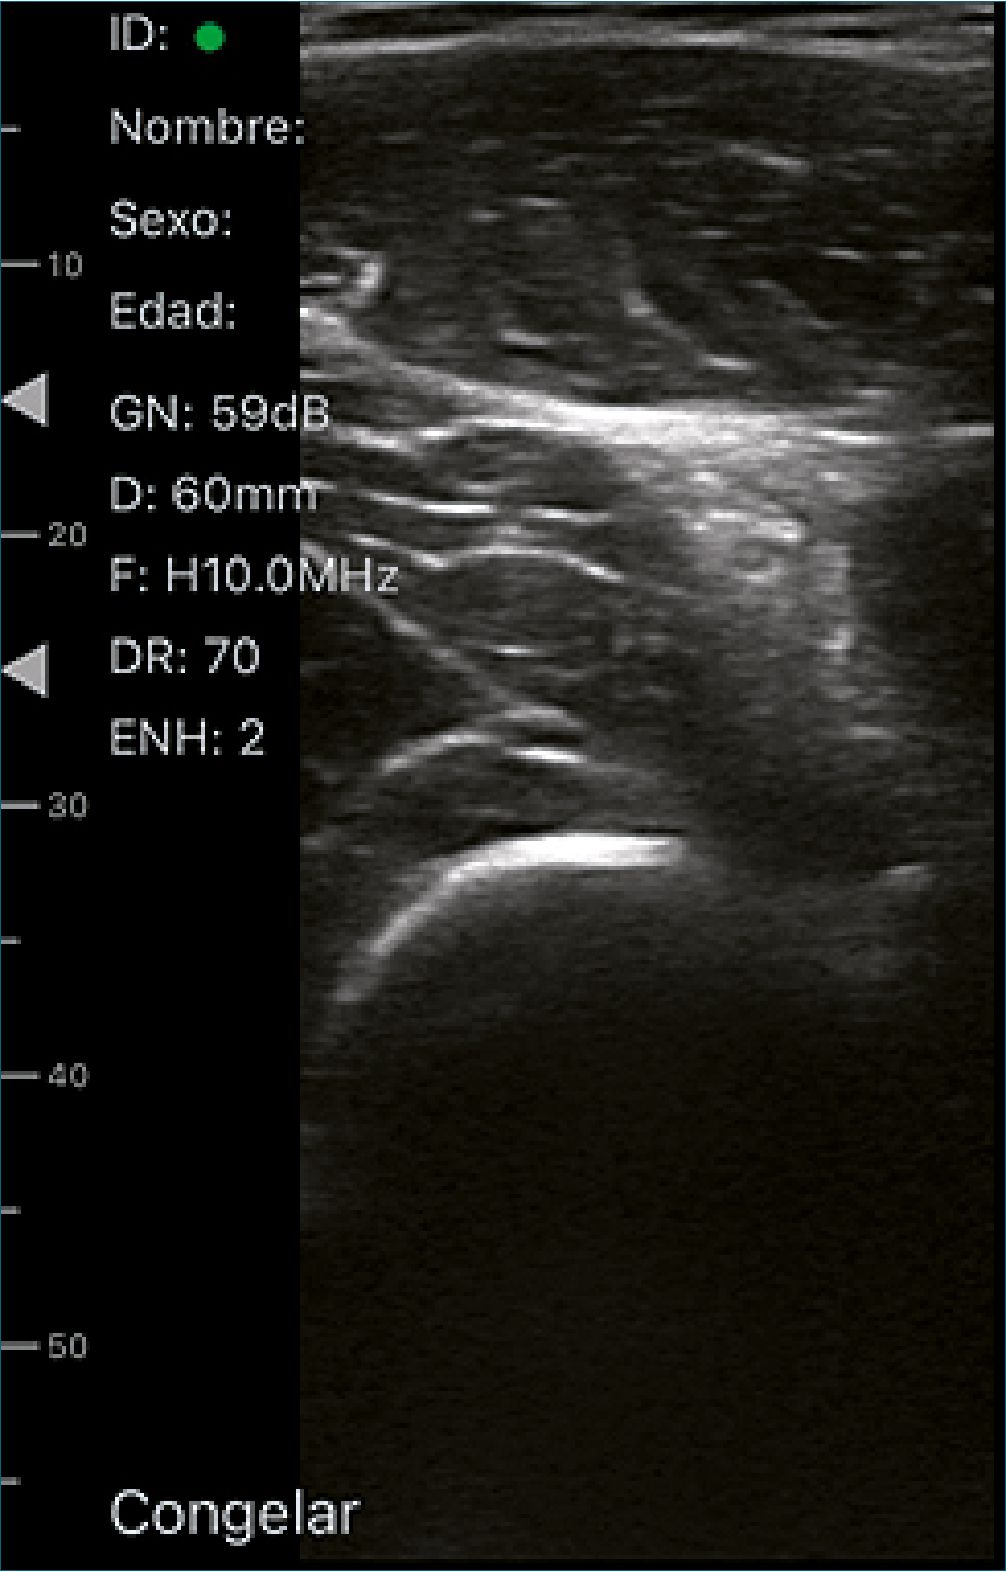

Bloqueo nervio ciático de fosa poplítea (Figura 2)

La fosa poplítea es un área en forma de diamante con el triángulo superior formado por los tendones del semitendinoso y semimembranoso medialmente y el tendón del bíceps femoral lateralmente. El nervio ciático se divide en el nervio peroneo común y el nervio tibial. El nervio peroneo común sale de la fosa poplítea lateralmente y el nervio tibial sale medialmente. La ramificación del nervio ciático tiene lugar en varios niveles por encima del pliegue poplíteo[33].

El paciente se coloca en decúbito supino, en muchos niños con parálisis cerebral, la pierna rotará externamente lo suficiente como para permitir que los nervios se acerquen medialmente. Para una sola inyección, se recomienda una técnica en el plano, ya sea desde la cara medial o lateral de la pierna. Con la ecografía, se puede identificar el nivel exacto de ramificación del nervio ciático; en este punto, la circunferencia combinada de los dos nervios será mayor que la circunferencia del nervio “ciático”; un bloqueo en esta ubicación proporciona un mayor contacto entre el anestésico local y el nervio[33].

Figura 2. Bloqueo nervio ciático de fosa poplítea.